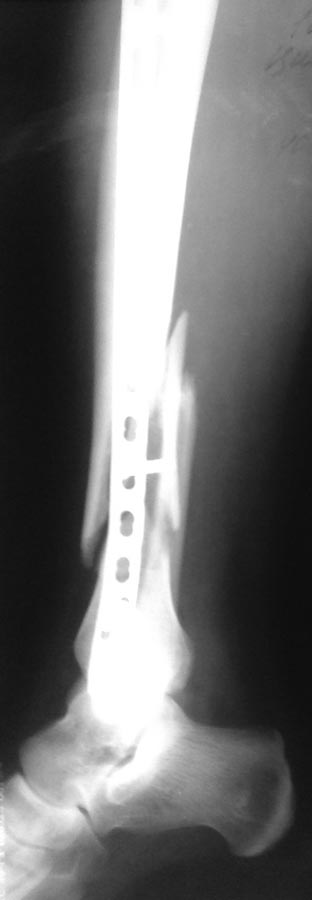

[Ortho] Деформация фиксатора после падения

первичные снимки и остальные качеством получше.

Имя     : lat.jpg

Тип     : image/jpg

Размер  : 31066 байтов

Url     : http://weborto.net:8080/pipermail/ortho/attachments/20121105/5ddbb42f/attachment-0006.jpg